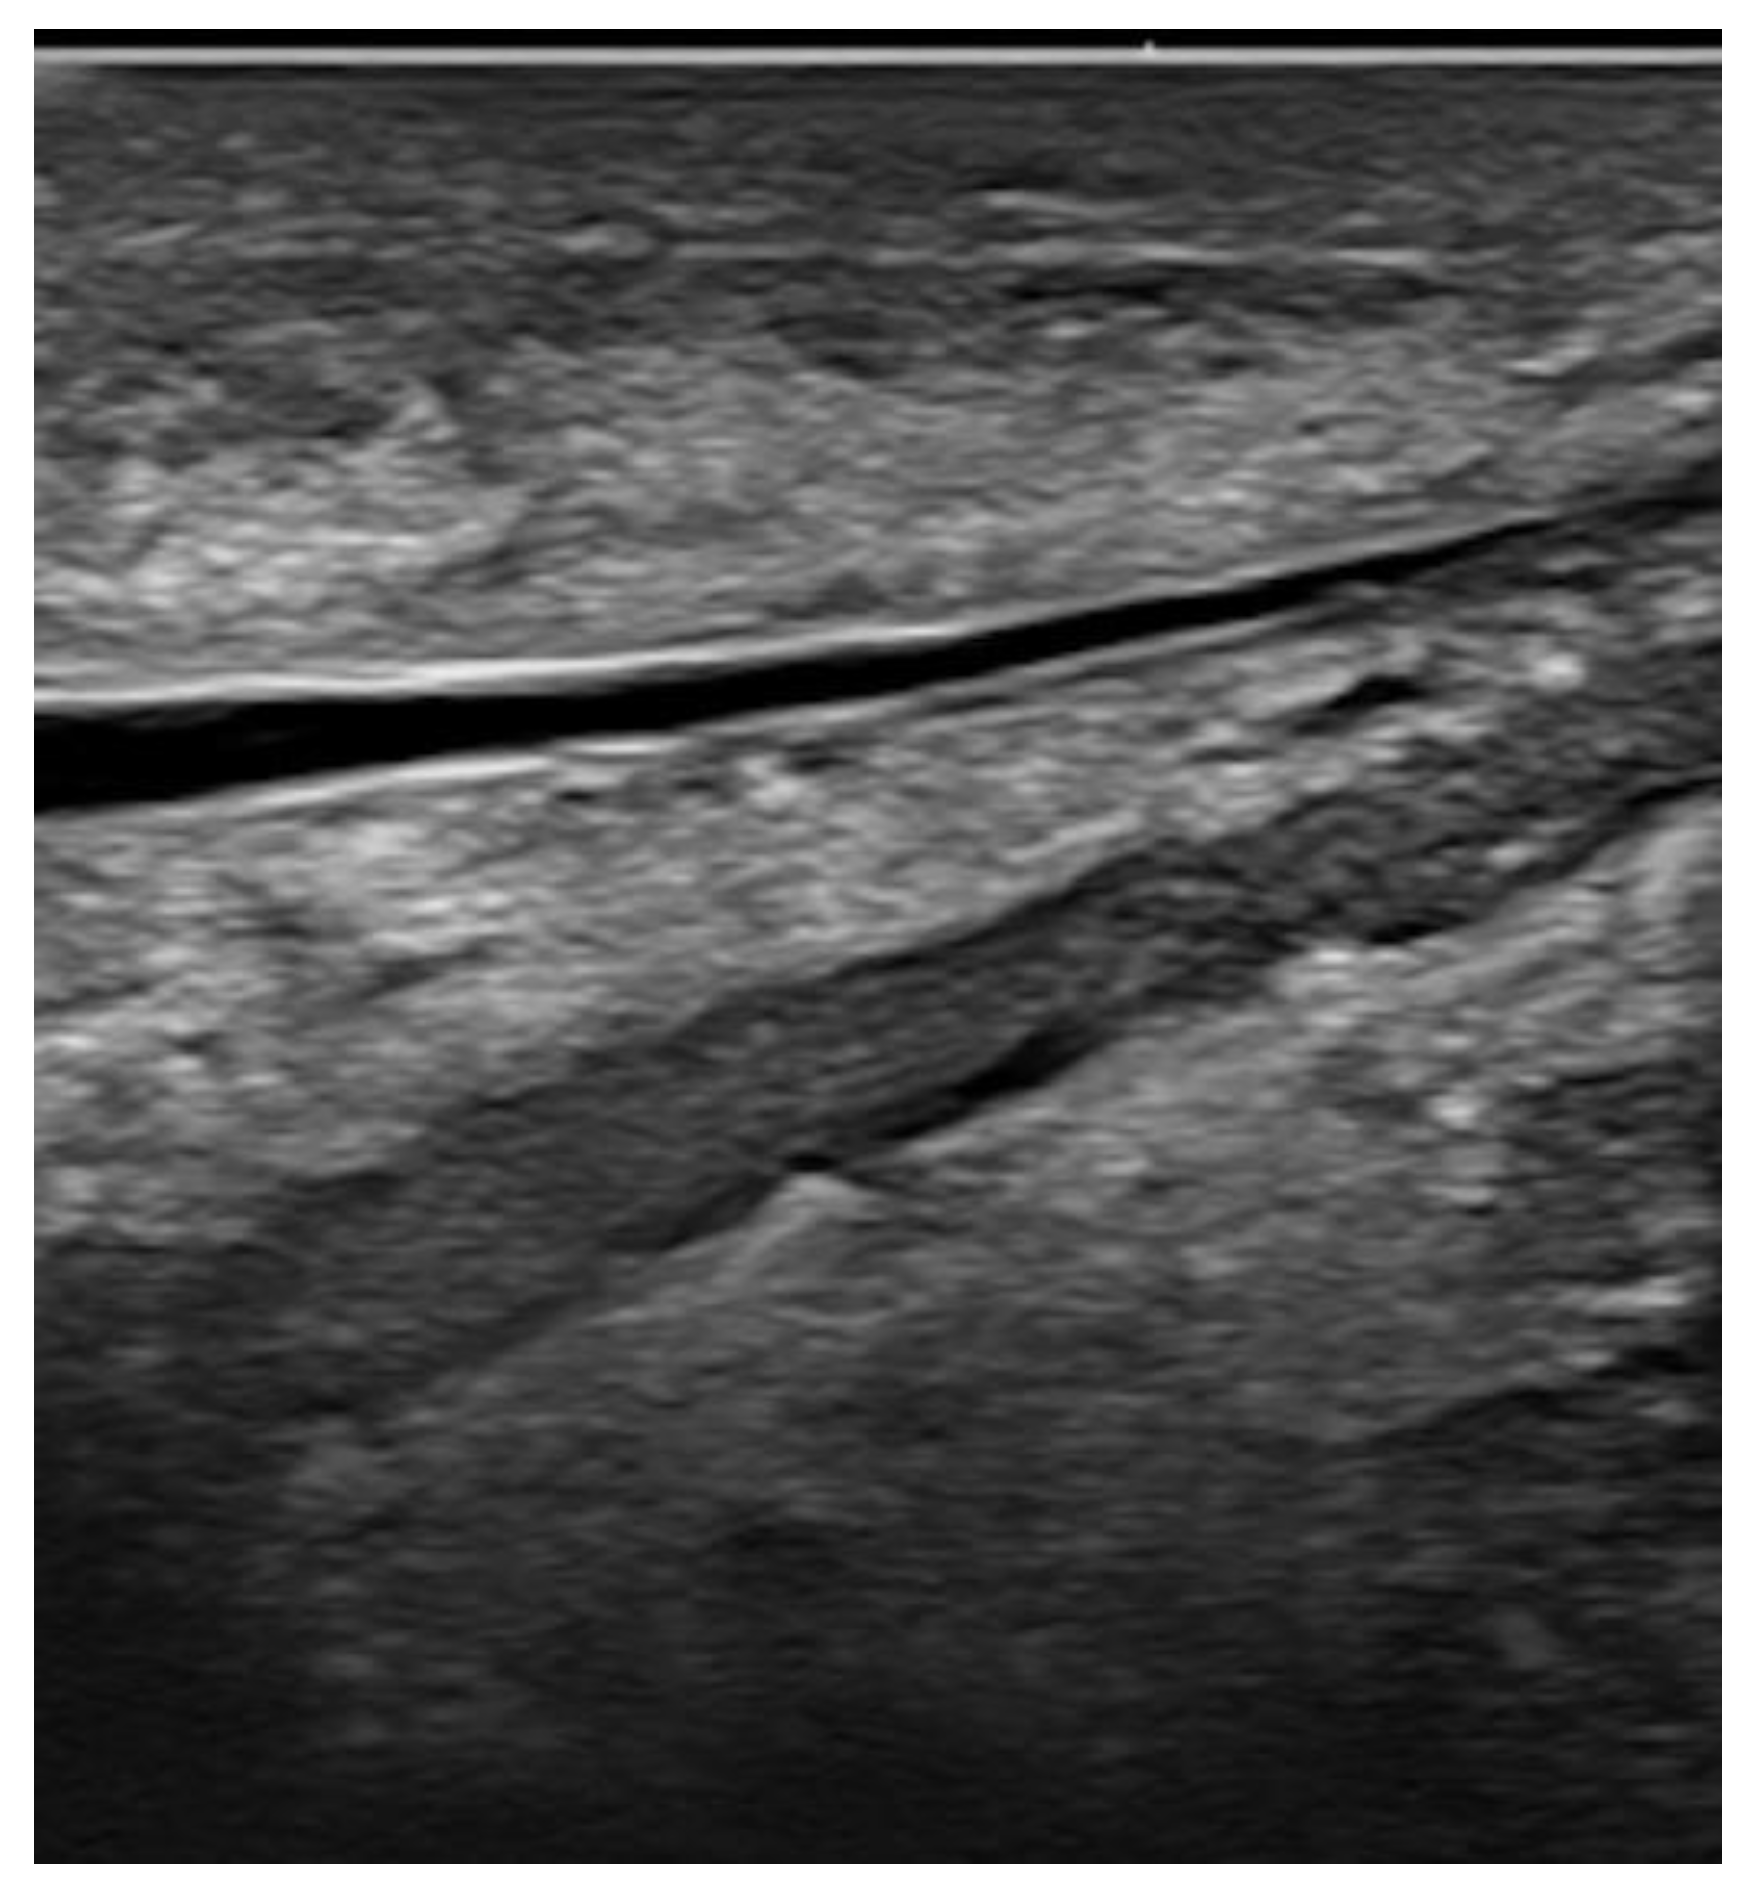

Figure 1. Breast vein imaged at 22 MHz. Note the high-quality details of the venous wall and lumen.